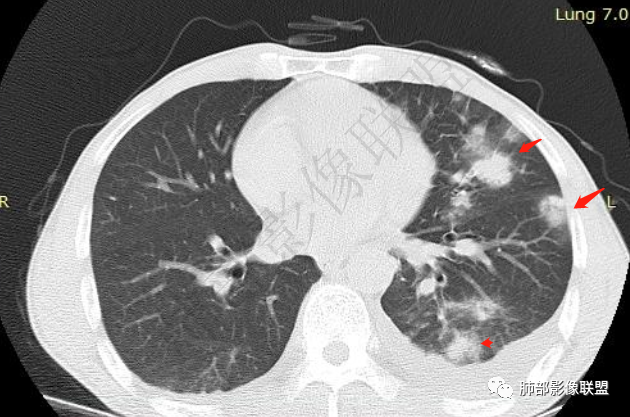

双肺多发大小不等结节影,边缘伴有磨玻璃影,边界欠清,部分与血管束相连,支气管似有穿行病灶内,结节有融合,左肺下叶厚壁空洞,伴有反晕征,左侧胸水,临床中年男性,发热40℃,CRP增高,感染性病变,1:类鼻疽伯克霍尔德菌(好发海南,影像表现也符合)

影像表现:双肺弥漫分布斑片影、实变影、磨玻璃影、结节影,晕征、反晕征,随机分布,部分病灶空洞形成前兆,左侧胸腔积液。

两肺多发斑片状实变影,周围GGO

单凭影像:鹦鹉热、军团要考虑,因为内部无坏死,非典型气道为主

我纠结的是,这是气道来源还是血播,如果血播加上海南下田,优先类鼻疽,如果气道,军团也要考虑,只是没见过军团反晕,除非免疫缺陷,混合感染。另外肺克,肺克好像气血皆可,后面反晕出洞,如果没有海南,也要考虑吧,肺克也是免疫妥协相关菌

早上这里是支持血播的

这些层面又像气道

这一类表现等于是病灶没有沿气道趋势,不支持以肺实质、支气管的分布区域,我认为是沿气道到播散,间质蔓延为主

影像表现:双肺多发结节、实变影,大部分病灶边界不清,随机分布趋势,左下肺“反晕征”,似有形成空洞趋势。左侧胸腔积液。治疗后复查 ,大部分病灶吸收好转,呈较为典型血播分布,肝脏低密度块影,边界不清,符合肝脓肿。